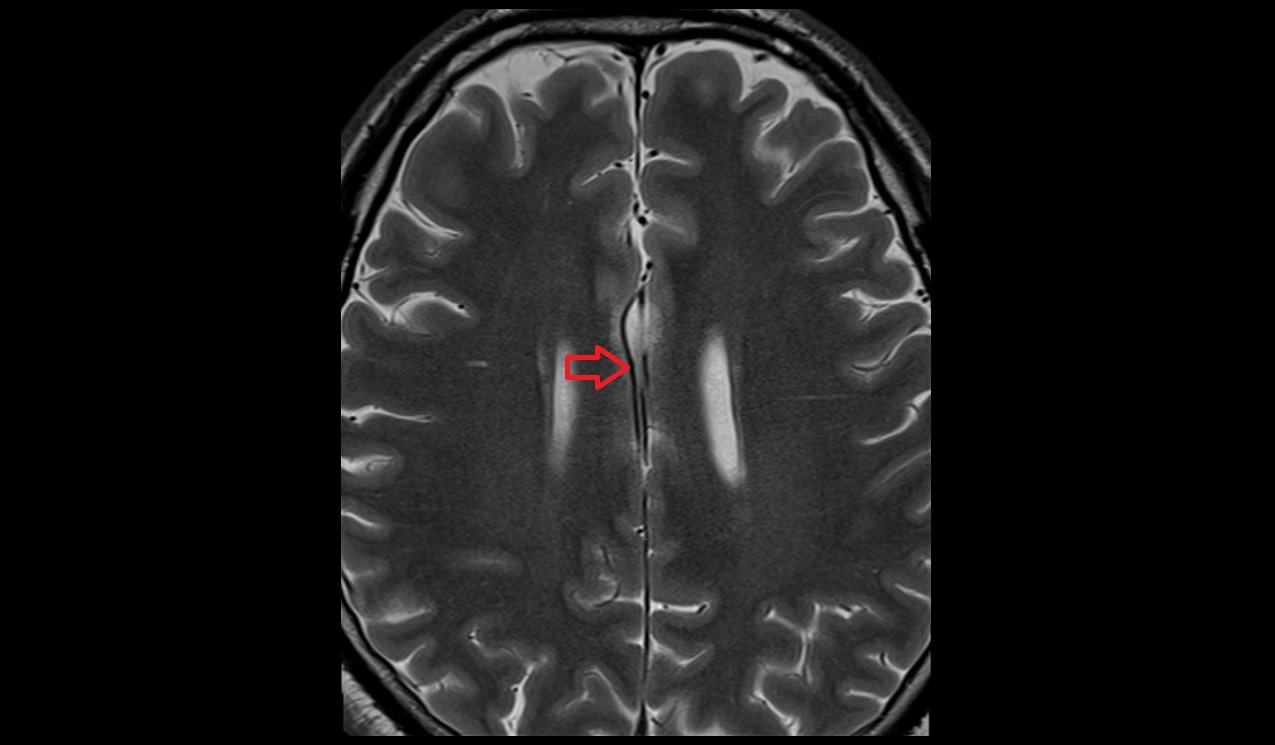

- Long medial striate artery